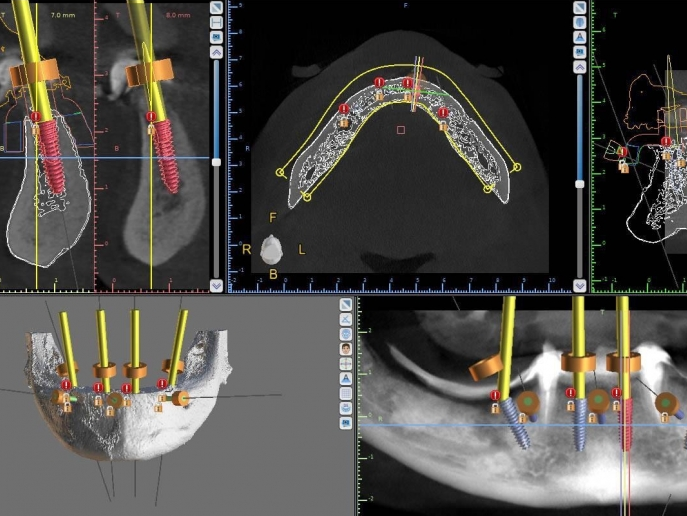

Vă prezentăm un caz All-on-4 finalizat cu succes cu ajutorul a 2 ghiduri chirurgicale realizate 100% cu ajutorul tehnologiei digitale.

Am folosit doua ghiduri: unul pentru osteoplastia crestei alveolare, iar cel de-al doilea pentru inserarea implanturilor.

• precizie în planificare;

• precizie în intervenții chirurgicale;

• precizie în implantarea minim invazivă;